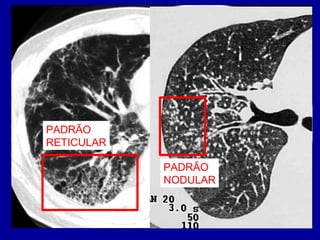

DOENÇAS DIFUSAS

PULMONARES

• RADIOGRAFIAS: TEM LIMITAÇÕES PARA A

CARACTERIZAÇÃO DESTAS LESÕES

• TC DE ALTA RESOLUÇÃO:

– DIAGNÓSTICO DIFERENCIAL

– CONTROLE EVOLUTIVO

– DEFINIR LOCAIS PARA BIÓPSIA

RADIOGRAFIA:

INFILTRADO RETICULAR

NA BASE E PERIFERIA

PULMONAR

PADRÃO

RETICULAR

NODULAR